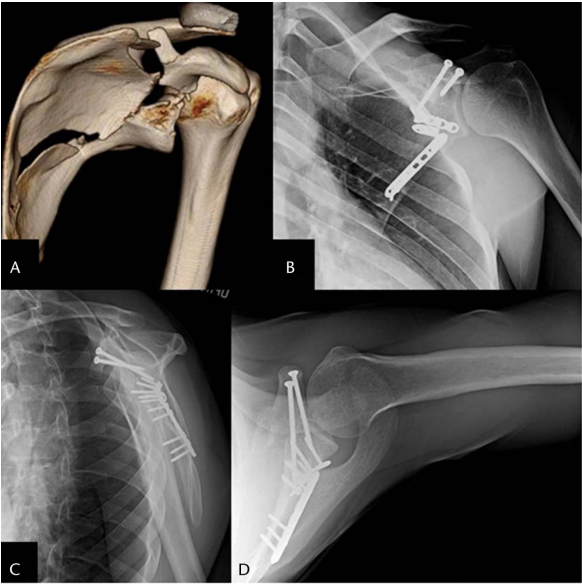

如果相关的肩盂和/或肩胛颈/体骨折正在通过后方 Judet 入路处理,那么可以完成带有附着喙突的肩盂上部的间接复位。具体来说,在某些常见的骨折类型中,例如 Eyres 喙突骨折 IV-VI 型,肩盂上骨折块附着在喙突上,并且当伴有移位的肩胛颈骨折时,根据骨折块的大小和骨折线的位置,首选入路可能是后路。改良的 Ideberg III 型肩盂骨折符合相同的描述。在这种情况下,从后路进行的固定间接固定了喙突。对于这种骨折变型,最有效的螺钉是从肩峰棘开始,向下打入肩胛颈,将上方冠状骨折块固定到其下方的宿主骨上。否则,可以按照上述描述,通过单独的前方肩关节入路处理喙突(图 6)。

图 6. A,一名患者的 3D CT 重建图像,显示其喙突移位性骨折延伸至肩盂关节面。如术后X光片(B-D)所示,采用钢板和螺钉组合固定这一更复杂的骨折类型。

在最终固定后,进行彻底的伤口冲洗和软组织闭合。切口部位用敷料妥善包扎,手臂用悬吊带固定。物理治疗方案集中在术后第一个月立即进行被动和主动 ROM。第二个月,重点转向实现力量和阻力训练,从 3-5 磅的重量开始,并根据耐受情况逐渐增加。所有限制在术后 3 个月解除。在肩胛下肌被松解的情况下,此方案延迟 3 周。